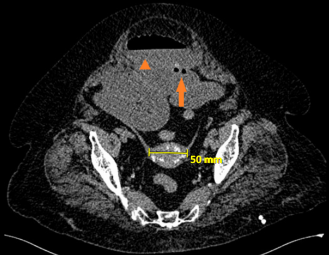

Image findings included radio-opaque image suggestive of a gallstone in 11 patients (68.7%), (Figure 6) bowel distention in 10 patients (62.5%) (Figure 7), and pneumobilia in 8 patients (50%) (Figure 8), all classical signs of Rigler´s triad.7

Figure 7 Fluid-filled dilated intestinal loops and hydro-air level (arrowhead), intestinal pneumatosis (arrow), and an endoluminal round-shaped calcium-density image of 50 mm are seen.

One 80years-old female with gastric outlet obstruction syndrome was diagnosed through a gastroduodenoscopy where the gallstone was found in the second portion of duodenum. (Figures 9A & B) An endoscopic attempt to extract the stone failed, so she was surgically intervened. Table 3 shows the details of our study population (Table 3).